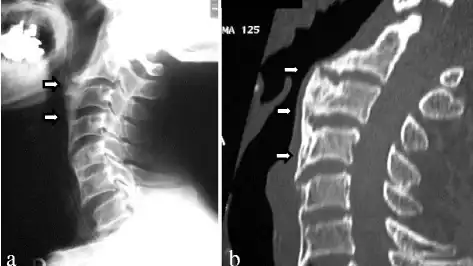

a) Recurrent ossification of anterior longitudinal ligament with anterior osteophytes arrows was present from C2 to C6 b) computed tomographic images of the cervical spine